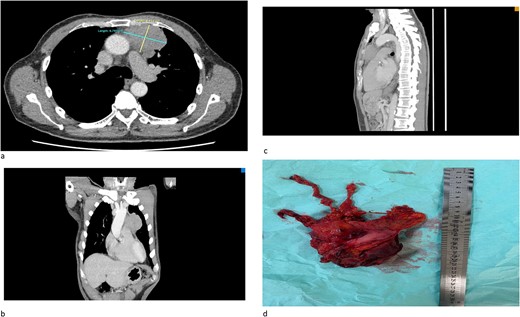

(a) An axial cut of a contrast-enhanced computed tomography (CECT) scan thorax showing an ill-defined anterior mediastinal mass measuring 4.8 cm × 6.7 cm. (b) A coronal view of a CT scan showing an ill-defined anterior mediastinal mass infiltrating the left upper and middle lobe lung. (c) A sagittal view of a CT scan showing an ill-defined anterior mediastinal mass. (d) A successful total thymectomy with R0 resection (microscopically margin-free resection) through a primary median sternotomy.

We would like to report a case of a 67-year-old male with no known co-morbidity who initially presented with generalized fatigue and hemoptysis. The serial bloods results are consistent with persistent hyponatremia. The patient was diagnosed with a duodenal ulcer after orogastroduodenoscopy and SIADH in view of persistent hyponatremia. Initial chest X-ray showed incidental findings of a widened mediastinum, and computed tomography (CT) scan of the thorax confirmed the presence of anterior mediastinal mass (Fig. 1a-c). CT-guided biopsy was inconclusive of the diagnosis and hence referred for surgical intervention. Serum osmolarity, urine osmolarity, and urine sodium were normal despite being followed up with SIADH. CT brain showed no evidence of intracranial involvement.